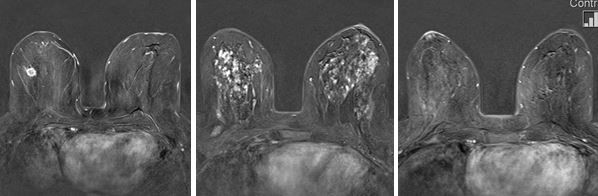

Ganz wichtig ist es, dass Sie sich in dieser Zeit nicht bewegen. Im letzten Drittel der Untersuchung wird Kontrastmittel über die Kanüle in eine Vene gespritzt. Gerade in der folgenden Aufnahmezeit von etwa 5 Minuten ist jede Bewegung zu vermeiden, da die entstehenden Aufnahmen computergestützt weiterbearbeitet werden, um die Kontrastmittelaufnahme des Brustgewebes optimal beurteilen zu können. Da bösartige Herde meist frühzeitig und kräftig Kontrastmittel aufnehmen, können sie innerhalb des normalen Gewebes erkannt werden (Abb. unten links). Weil hormonelle Einflüsse auf das Brustgewebe zu falsch positiven Befunden führen können (Abb. unten Mitte), sollte die Untersuchung in der zweiten Zykluswoche durchgeführt werden. In dieser Zeit ist die Beurteilbarkeit der Untersuchung am besten (Abb. unten rechts).